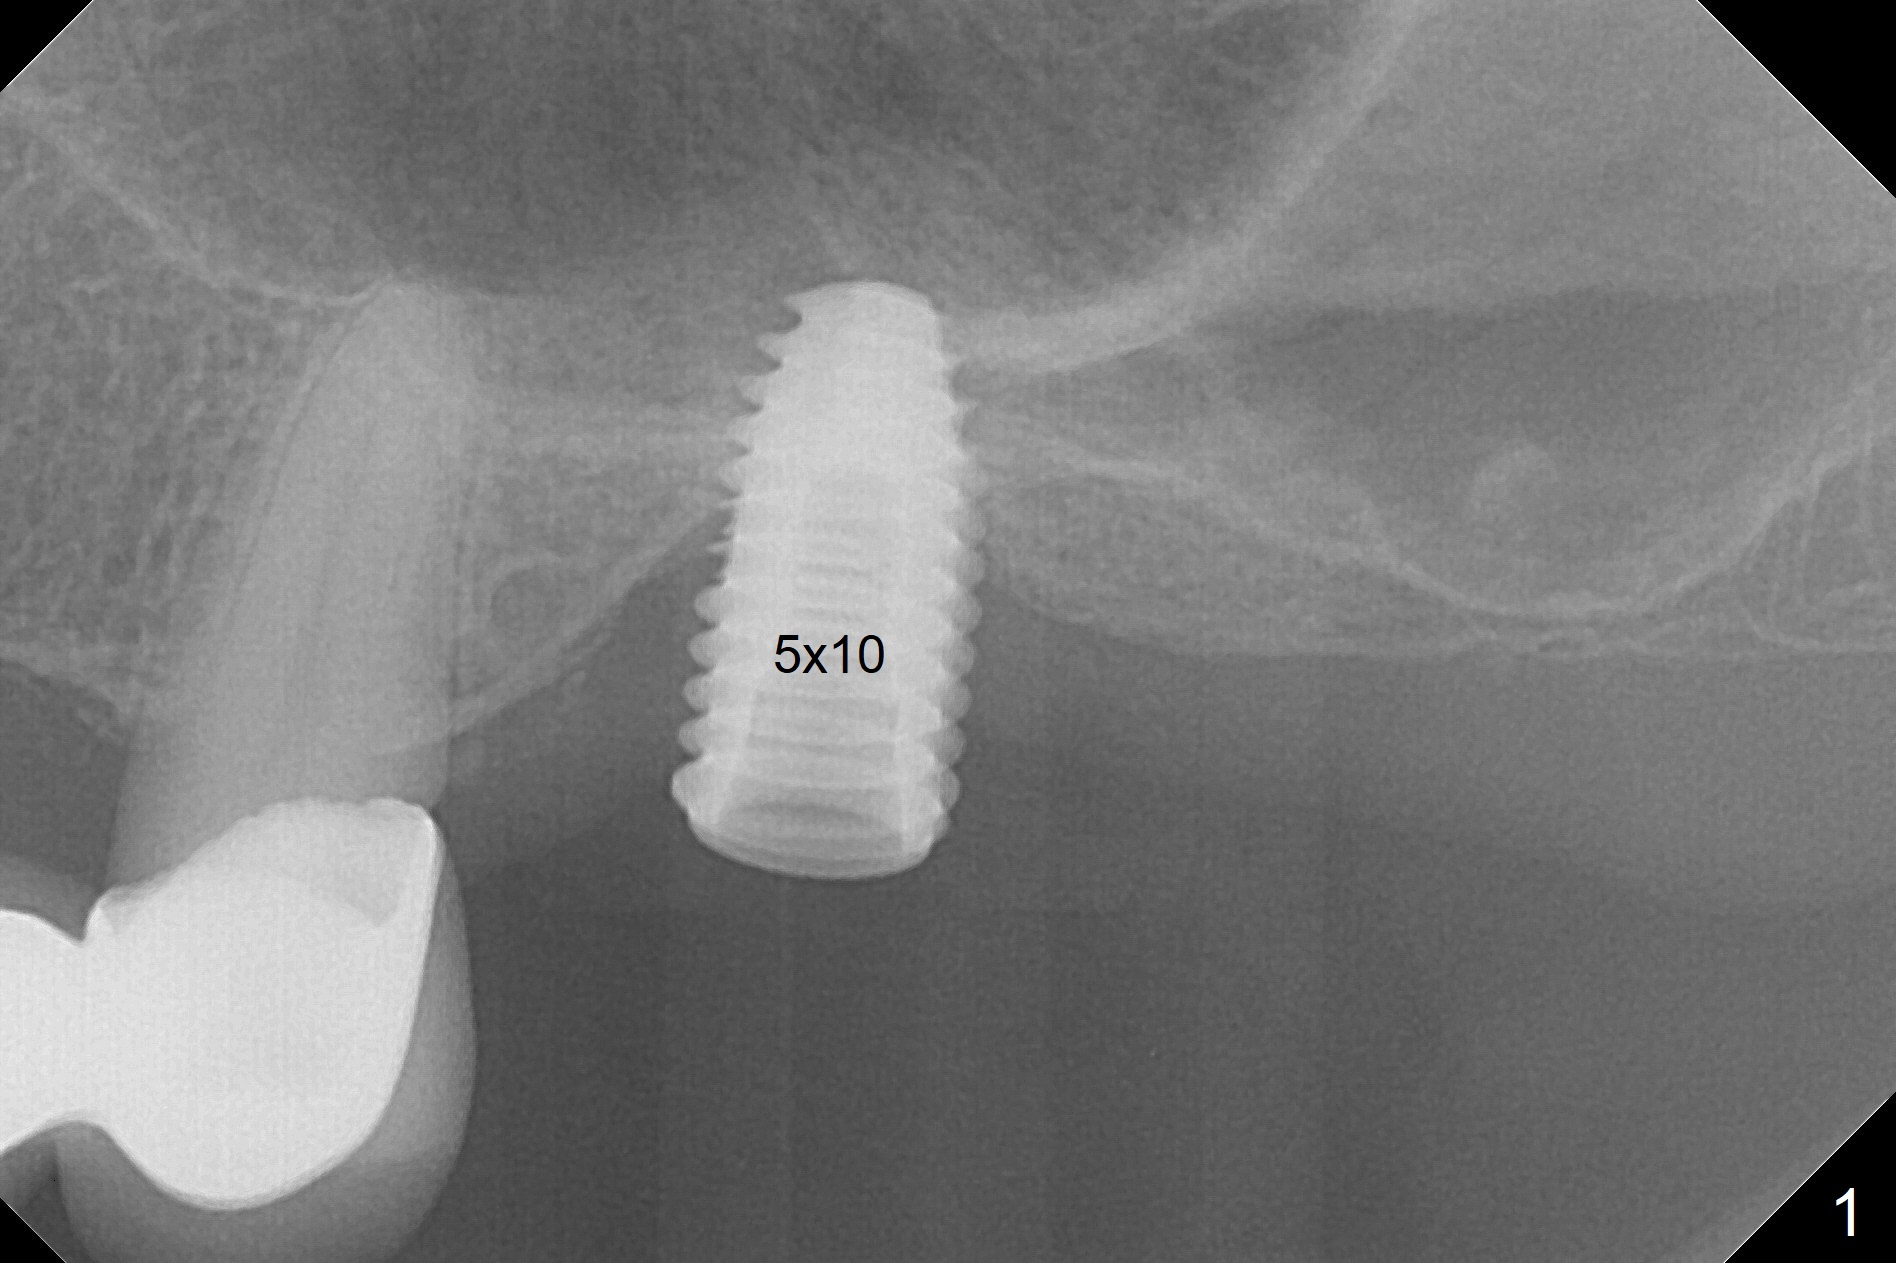

When the non-osteointegrated implant is removed, the sinus membrane is found to have been perforated. There is a history of clear discharge immediately postop ~ 1 year ago. Against the common wisdom, a 5x10 mm dummy implant is inserted with intention to correct the trajectory and 50 Ncm (Fig.1). With placement of Osteogen plug (presumably for repair of the perforation) and limited amount of Vanilla at the osteotomy, a 5x7.3 mm IS implant with SLA surface treatment is placed (Fig.2, ~ 40 Ncm). When the implant is further seated (Fig.3 arrow with bone graft coronally *)), its trajectory is within the normal limit (Fig.4 blue line). If the implant fails again, it must be due to the mild sinus infection. Bone graft, or preferably Osteogen Plug (collagen with osteoconductive ability) should have been done first. Mild tenderness exists with use of Water Pik 7 months post 2nd placement (Fig.5). Uncover shows that the implant is stable. A 6x3 mm healing abutment is placed. Next appointment a temporary crown will be fabricated for progressive loading. The abutment screw needs retightening 8 months post cementation, probably related to poor crown/implant ratio and missing 2nd molar (Fig.6).